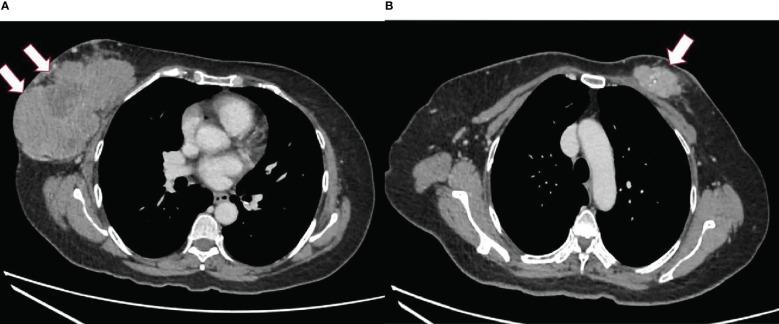

A 57-year-old Malay nullipara initially presented with a right breast lump that was increasing in size but defaulted follow-up. Two years later, she developed a contralateral breast lump. She only returned to the hospital when the right breast lump had become painful, 4 years from its onset. The biopsy of the right breast lump was a phylloides tumor and that of the left breast lump was a carcinoma. She had bilateral palpable axillary lymph nodes. She underwent bilateral mastectomy and axillary dissection. The pathology report confirmed the right breast lesion to be a malignant phylloides and the left breast lesion to be a carcinoma (pT3N2). She declined adjuvant treatment. A year after the surgical operation of the metachronous lesions, she had a right chest wall recurrence with widespread pulmonary metastases. She was given palliative chemotherapy but succumbed several months later.

一名57岁未育马来女性最初因右乳肿块就诊,肿块逐渐增大,但她未按要求进行随访。两年后,她对侧乳房出现肿块。自右乳肿块出现4年后,当肿块开始疼痛时,她才再次回到医院。右乳肿块活检为叶状肿瘤,左乳肿块活检为癌。她双侧腋窝可触及肿大淋巴结。她接受了双侧乳房切除术及腋窝淋巴结清扫术。病理报告证实右乳病变为恶性叶状肿瘤,左乳病变为癌(pT3N2)。她拒绝辅助治疗。异时性病变手术一年后,她出现右胸壁复发并伴有广泛肺转移。她接受了姑息化疗,但数月后仍去世。